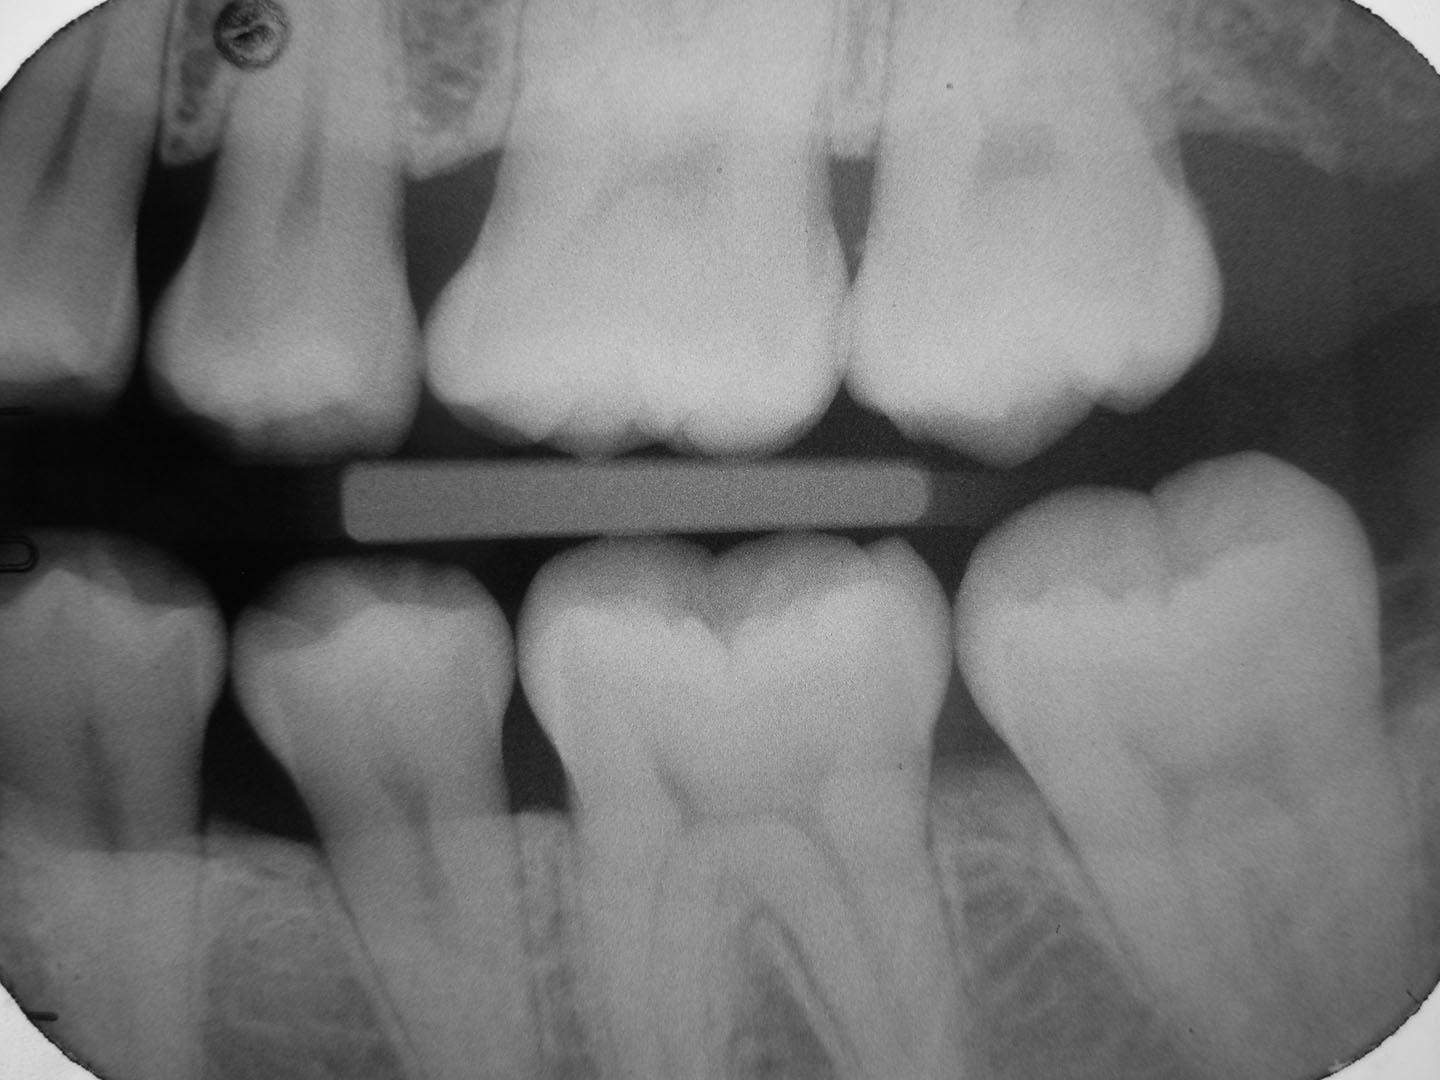

You will need an electronic copy of your x-rays from the dentist prescribing the procedure. Click the link below to upload this information to our AI Evaluation partner KELLS and complete the questionnaire. After the AI has evaluated your images, you will receive a detailed, written report on the findings, with treatment recommendations by a TeleDentist in your state. If you want to discuss your treatment options with your TeleDentist, simply book an appointment on our secure telehealth platform. You can have a face-to-face conversation with the TeleDentist to go overtreatment options, referrals, and more!

Dental cavities with severity estimation

Gum inflammation (gingivitis)

Gum recession

Plaque Fracture (cracked tooth)